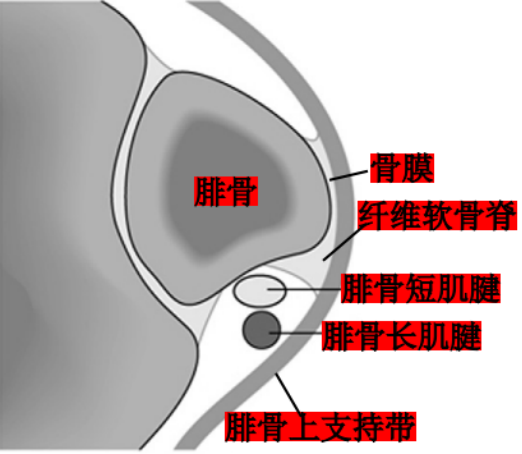

腓骨长短肌位于小腿外侧间隔。

腓骨长肌(PL):起于腓骨头、腓骨外侧面上2/3和小腿深筋膜,止于第1跖骨外侧及毗邻的第1楔骨的内侧,至小腿下1/3处,长肌移行为肌腱,在它到达止点前的行程中有三个弯曲,第一个在外踝顶点,第二个在跟骨外侧壁的腓骨肌滑车下,第三个在骰骨结节处经90°转到足底。

腓骨短肌(PB):起于腓骨外侧面下2/3及前后肌间隔,短肌至外踝的后下方始为移行为肌腱,紧贴于外踝后方,通过外踝顶点转向足外侧前方,经过跟骨外侧壁腓骨肌滑车上方最后止于第五跖骨基底。

腓骨肌腱鞘:起于外踝顶点上3.5cm并向远端延伸4cm,在腓骨的远端,腱鞘分为两部分,腓骨长、短肌腱各自进入独立的滑液鞘。

腓骨外踝窝:外踝的后方近端较宽广,远端呈锥形变小并有一浅的沟。

纤维软骨脊(FCR):腓骨外踝窝的外侧缘有一纤维软骨形成的缘,构成了窝的结构。该纤维软骨脊近端明显,向远端渐变小,使得沟的整体深度增加了2-4mm,且形状更适于容纳腓骨肌腱,从而促进应力分散。

腓骨肌支持带:

腓骨上支持带(SPR):起于腓骨外侧面和腓骨外踝窝,绕过腓骨肌腱后止于跟骨和跟腱外侧。SPR没有直接牢固固定于纤维软骨脊,而是与腓骨外侧面的骨膜融合。

下支持带(IPR):前上方与伸肌支持带外侧根延续,后下方附着于跟骨前部外侧面。在跟骨滑车上下形成两个纤维管道固定肌腱于跟骨外侧壁。

相关文献在单纯切断下支持带后,腓骨肌腱的稳定性不受影响,但单纯切断上支持带后,将跟骨外翻后腓骨肌腱有脱位趋势。因此认为:腓骨肌上支持带是稳定腓骨肌腱的重要结构。

腓骨外踝窝、纤维软骨脊和腓骨上支持带是稳定腓骨肌腱的基本结构。其中又以腓骨肌上支持带最为重要。